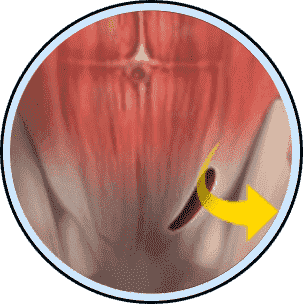

Hip problems don’t always start in your joints. In many patients, factors like inflammation, metabolic health, and tissue quality influence how early hip pain and degeneration appear.